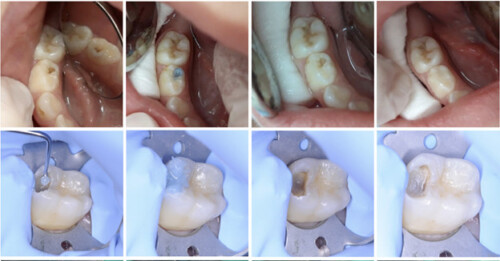

Hình 2: Làm sạch lỗ sâu với BRIX3000, không sử dụng tay khoan

Việc sử dụng BRIX3000 làm sạch lỗ sâu một cách không sang chấn, không dùng tay khoan, thực hiện dễ dàng là giải pháp thay thế tốt cho những bệnh nhân có lo lắng nha khoa, sợ tay khoan, từ đó cải thiện được sự tự tin và hợp tác của họ trong các thủ thuật điều trị nha khoa trong tương lai. Bên cạnh đó, trong những giai đoạn nhạy cảm với giọt bắn như thời kỳ COVID – 19, việc làm sạch bằng tác nhân cơ hóa học cũng là lựa chọn an toàn hơn so với phương pháp thông thường.